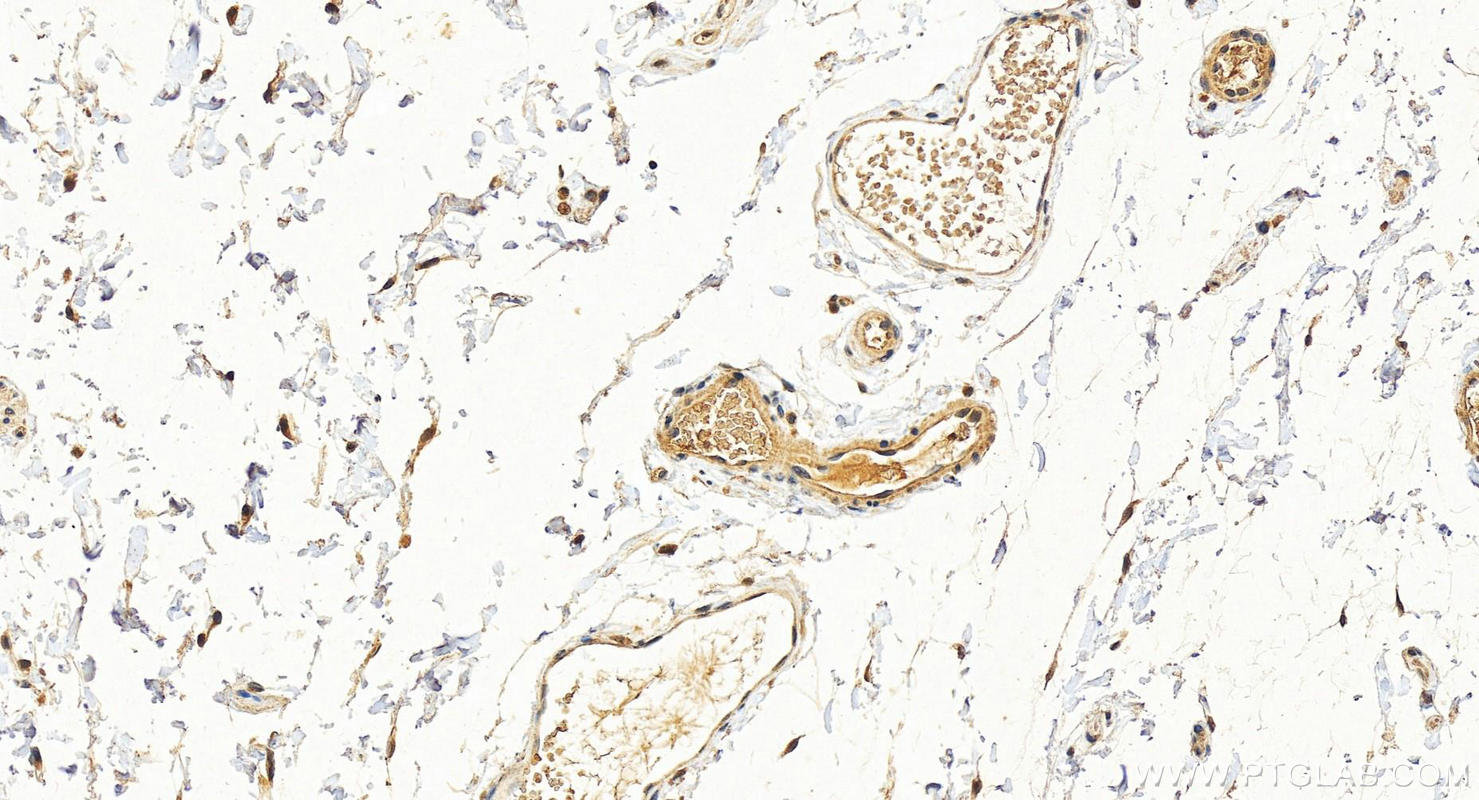

| Positive IHC detected in | human colon tissue, human breast cancer tissue, human brown disease, human cervical cancer tissue, human liver cancer tissue, human lung cancer tissue, human thyroid cancer tissue, mouse colon tissue, rat colon tissue Note: suggested antigen retrieval with TE buffer pH 9.0; (*) Alternatively, antigen retrieval may be performed with citrate buffer pH 6.0 |

| Immunohistochemistry (IHC) | IHC : 1:150-1:600 |

14965-1-AP targets Cytokeratin 19 in WB, IHC, IF/ICC, IF-Fro, ELISA applications and shows reactivity with human, mouse, rat samples.

Cytokeratin 19 (CK19 or KRT19) is a type I (acidic) cytokeratin. It is an intermediate filament protein providing structural rigidity and multipurpose scaffolds in epithelial cells. CK19 is often overexpressed in various cancers (e.g., hepatocellular carcinoma [HCC], pancreatic adenocarcinoma, lung cancer) and serves as a biomarker for hepatic progenitor cells (HPCs) associated with poor prognosis in HCC patients . Additionally, CK19 expression is common in pancreatic and gastrointestinal adenocarcinomasand has been studied as a potential diagnostic and prognostic marker for pancreatic neuroendocrine tumors (PNETs), where positive CK19 expression correlates with poor prognosis. Serum CK19 fragments (e.g., CYFRA 21-1, CK19-2G2) have been investigated as tumor markers for lung and breast cancer, with preoperative levels associated with metastasis and survival. This antibody, generated against full length KRT19 protein, also recognizes KRT17, another type I keratin homologous to KRT19.